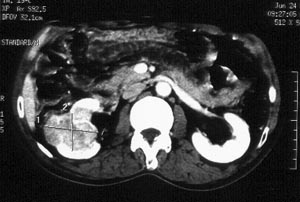

男性,56岁。右腰部不适2月。无血尿,无尿频尿急尿痛。b超提示:右肾下极占位。

ct平扫加增强扫描:右肾中下极肾盂外侧段实质见分叶状软组织密度肿块,截面大约56x45mm,向外突破肾包膜,向内突入肾盂,平扫密度略不均,ct值32-37hu。c+见病灶不均匀轻-中度强化,内有未强化坏死区。右侧肾周筋膜增厚,右肾内前方见肿大淋巴结。

ct诊断:右肾癌,ct表现见上述,伴同侧腹膜后淋巴结转移。

手术所见:右肾大小15x7cm,背侧有肿物突出肾包膜,大小7x4cm。行“右肾癌根治术”。

手术病理:

透明细胞癌(ⅰ-ⅱ级)